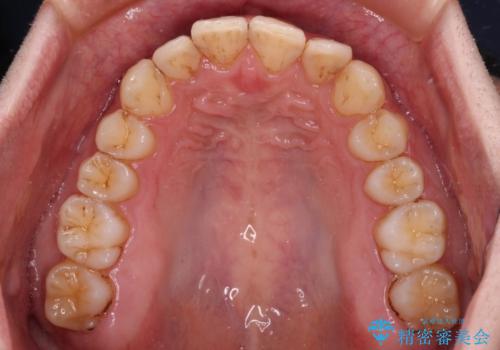

前歯のデコボコをスッキリ改善 インビザライン矯正

- 上下前歯のデコボコを気にして来院された患者様です。

全体的に叢生は軽度であったため、インビザラインにて矯正治療を行うこととしました。

デコボコの改善はもちろん、下顎前歯が隠れてしまうディープバイトも一緒に改善することができ、奥歯への負担を軽減することができました。